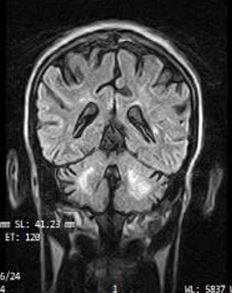

Cerebrovascular Neurology | Nov 17, 2025

Primary Antiphospholipid Syndrome Presenting as a Stroke in a Young Male

Antiphospholipid syndrome (APS) is an autoimmune disorder characterized by recurrent thrombosis and/or pregnancy morbidity in the presence of specific antiphospholipid...Read More